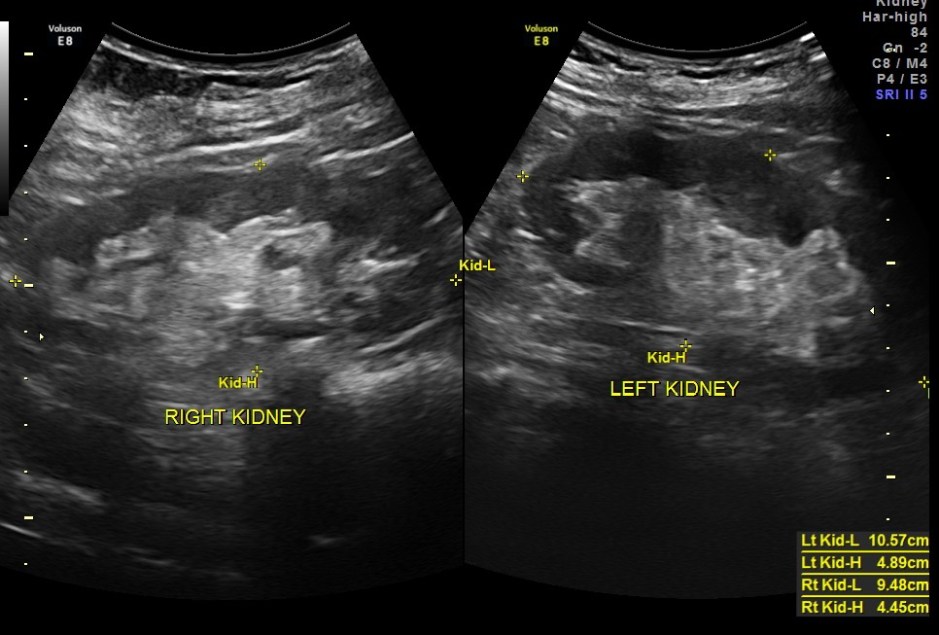

pancreas, spleen and both kidneys were normal.